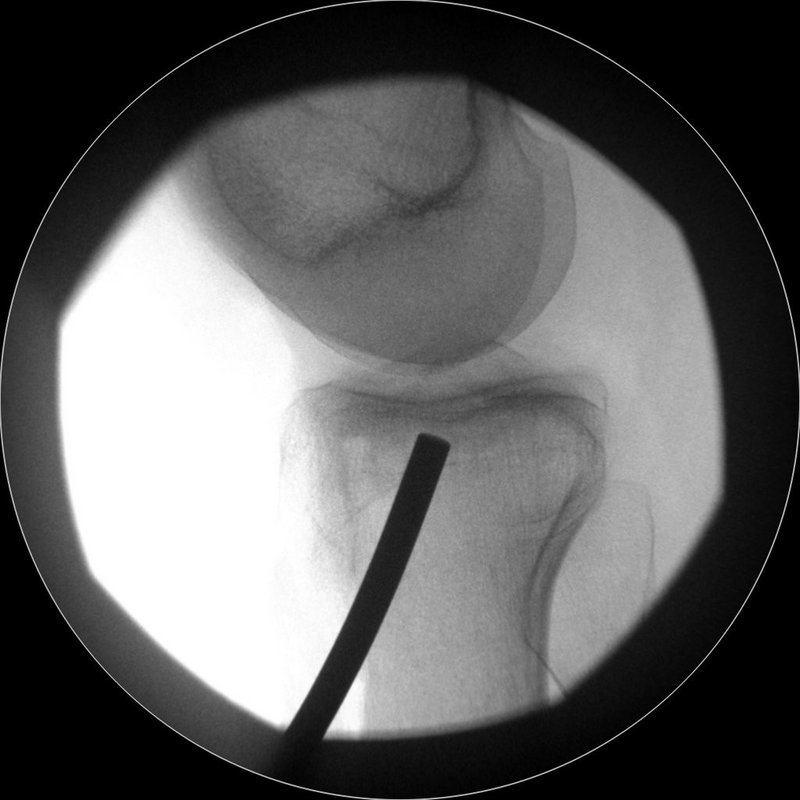

Eine der häufigsten Sportverletzungen im Bereich des Kniegelenkes ist die vordere Kreuzband-Ruptur. Vor allem bei jungen, sportlich aktivem Patienten ist oftmals eine sogenannte VKB-Ersatzplastik notwendig. Goldstandard ist der Ersatz des gerissenen Kreuzbandes durch eine körpereigene Sehne, ggf. können noch stehende Restfasern als Leitstruktur belassen werden. Hierzu stehen verschiedene Transplantate zur Verfügung (Hamstring-Sehnen, Quadrizepssehne, …) die individuell ausgewählt werden. Zusatzverletzungen des Meniskus oder der Seitenbänder werden ebenfalls im Rahmen der Operation behandelt. Das Kreuzband wird über Bohrkanäle an die anatomische Position gebracht und dort mittels sog. Interferrenzschrauben im Kanal verblockt.

Re-Ruptur des vorderen Kreuzbandes

Im Falle von Re-Rupturen des vorderen Kreuzbandes ist in manchen Fällen keine direkte einzeitige Versorgung mit einem neuen Kreuzband möglich, z.B. wenn sich die Bohrkanäle geweitet haben. Dann müssen die alten Kanäle in einem ersten Eingriff gefüllt werden und die erneute Kreuzbandplastik erfolgt nach einigen Monaten. Auch Achs-Fehlstellungen, die das Risiko einer weiteren Ruptur begünstigen würden, werden abgeklärt. Insbesondere eine X-Bein-Stellung oder eine Verkippung des Schienbeinkopfes (sog. „Slope“) gelten hier als Risikofaktoren, die ggf. vor einer erneuten Versorgung mit einem Kreuzband behandelt werden müssen – ebenso wie periphere Instabilitäten, die ebenfalls mit abgeklärt werden müssen.